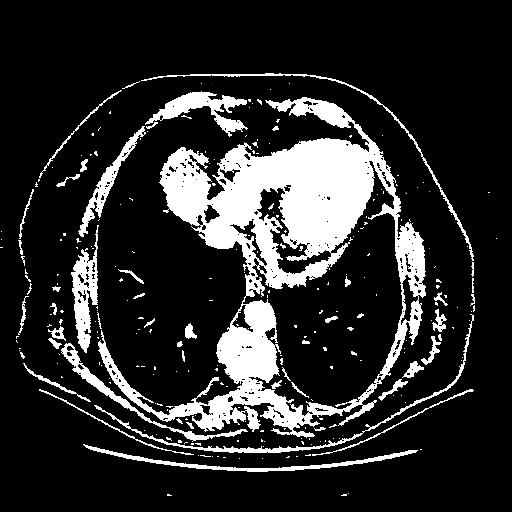

Original VENOUS CT scan

Full window (WL 1023.5, WW 4095 β†’ Low βˆ’1024, High +3071)

Actual HU range: [-1024.0, 3071.0]